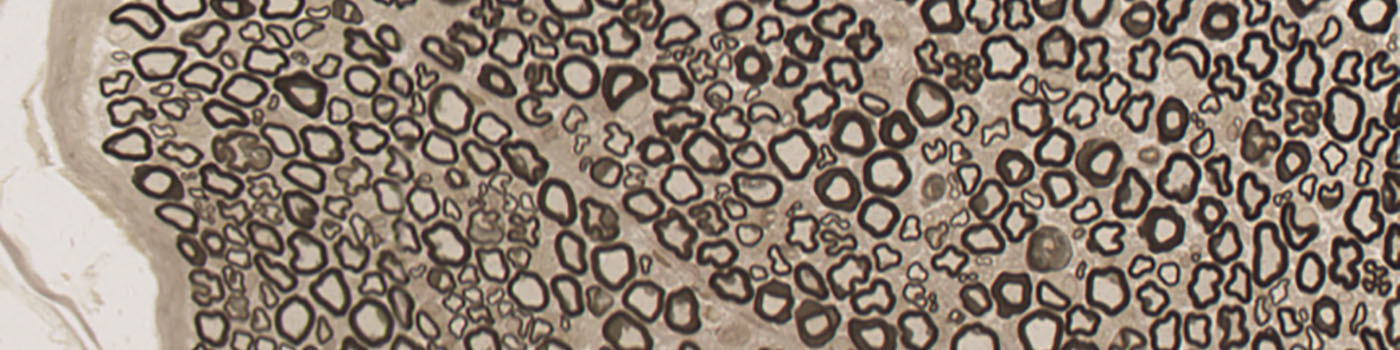

Figure 1

Nerve fiber bundles.

A close-up of a nerve fiber bundle, showing several axons with associated myelin.